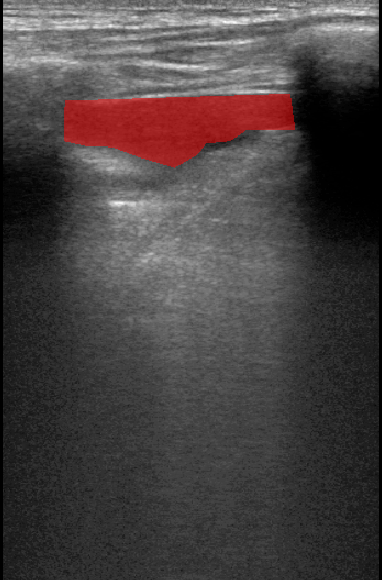

A total of 143 images were acquired from 59 patients. The images were obtained at the left and right PLAPS (PosteroLateral Alveolar and/or Pleural Syndrome) and subcostal views [4] with linear array and curved array (abdominal) ultrasound probes. The data were split according to the use of these probes into two datasets of 51 and 92 images, respectively for linear array and curved array. We denote these datasets as Dataset A (linear array) and Dataset B (curved array). All images were annotated at the time of acquisition to measure the extent of the effusion. These annotations consisted of small crosses at the top and bottom of the deepest area of effusion. See Figure 1 (left column) for example images.

Before being used for training and evaluating the models, each image was automatically cropped using a rectangular/cone mask to remove non-imaging content. Next, we applied an inpainting text algorithm using keras-ocr followed by template matching and edge detection algorithms from opencv to remove the annotations that were added to the images to measure the effusion. Examples of the outputs of this preprocessing are shown in Figure 1 (centre column).

All images in both datasets were manually segmented using the ITK-SNAP software [14] (www.itksnap.org) by a trained observer. Examples of ground truth segmentations are shown in Figure 1 (right column). These segmentations acted as ground truths for training and evaluating the proposed models. Additionally, a second trained observer performed independent segmentations of subsets of 10 random images each from the two datasets. These were used to compute an estimate of inter-observer variability in the manual segmentation process.

Qualitative prediction results of the two proposed models (baseline nnU-Net and nnU-Net with coordinate convolutions) on the two datasets are shown in Figure 2. Tables 1 and 2 summarise the quantitative performances in terms of DSC and area statistics. Histograms of the DSC values are shown in Figure 3. The median DSCs between the manual segmentations on the subsets of 10 images (i.e. the estimates of inter-observer variability) are also shown in Table 1.

It can be seen that, despite having fewer images, the baseline model for Dataset A obtained a higher median DSC than the model for Dataset B. For Dataset A the coordinate convolution model improved the DSC and reduced the area error and bias. In two-tailed Wilcoxon signed rank tests (0.05 significance) the difference between the baseline DSC and that of the coordinate convolution model was found to be statistically significant for Dataset A () but there was no statistically significant difference for Dataset B (). Interestingly, for both Dataset A and Dataset B, both the baseline and coordinate convolution models performed better than the estimate of inter-observer variability. However, we note that the inter-observer variability is quite high (i.e. median DSCs of 0.78 and 0.71), likely reflecting the difficulty and partly subjective nature of the effusion segmentation task. Therefore, it seems likely that the deep learning models are learning to segment effusion in the style of the main observer, which may not always be consistent with the second observer. In addition, the histograms shown in Figure 3 suggest that there are a significant number of failure cases in the outputs of both models (although fewer for the coordinate convolution model for Dataset A), again reflecting the difficulty of the task.

Rows 1-2: Dataset A. Rows 3-4: Dataset B.